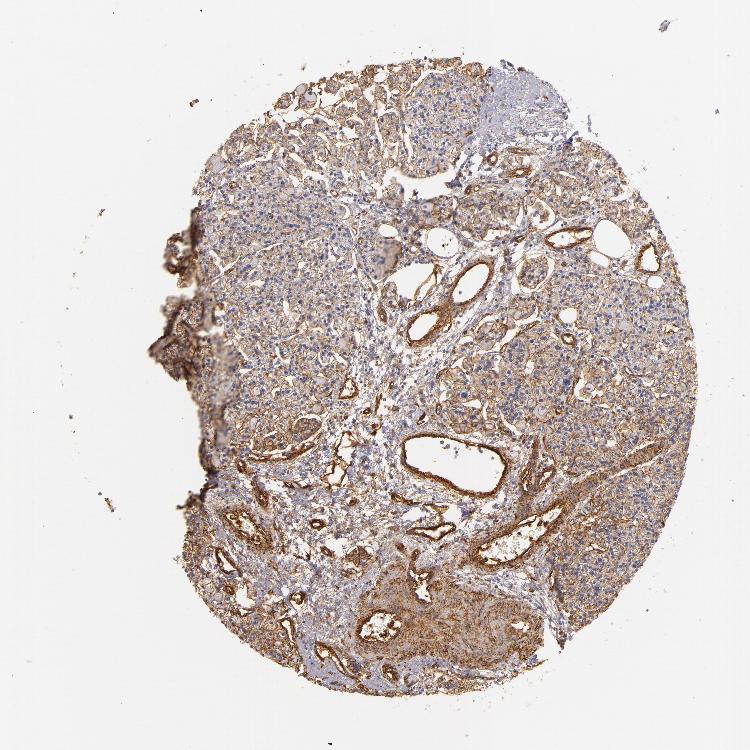

TISSUE PRIMARY DATA PARATHYROID GLAND Show tissue menu

PARATHYROID GLAND - Antibody stainingi

Antibody staining in the annotated cell types in the current human tissue is reported as not detected, low, medium, or high, based on conventional immunohistochemistry profiling in selected tissues. This score is based on the combination of the staining intensity and fraction of stained cells.

Each image is clickable and will lead to virtual microscopy that enables deeper exploration of all samples and also displays staining intensity scores, fraction scores and subcellular localization as well as patient and tissue information for each sample.

Antibody HPA011906Antibody CAB002428

Glandular cells MediumMedium